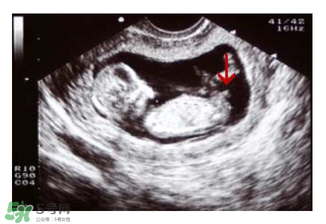

如果媽媽是孕晚期,也可以看B超圖,對(duì)著你的,一般是女寶寶,背著的,一般是男寶寶。